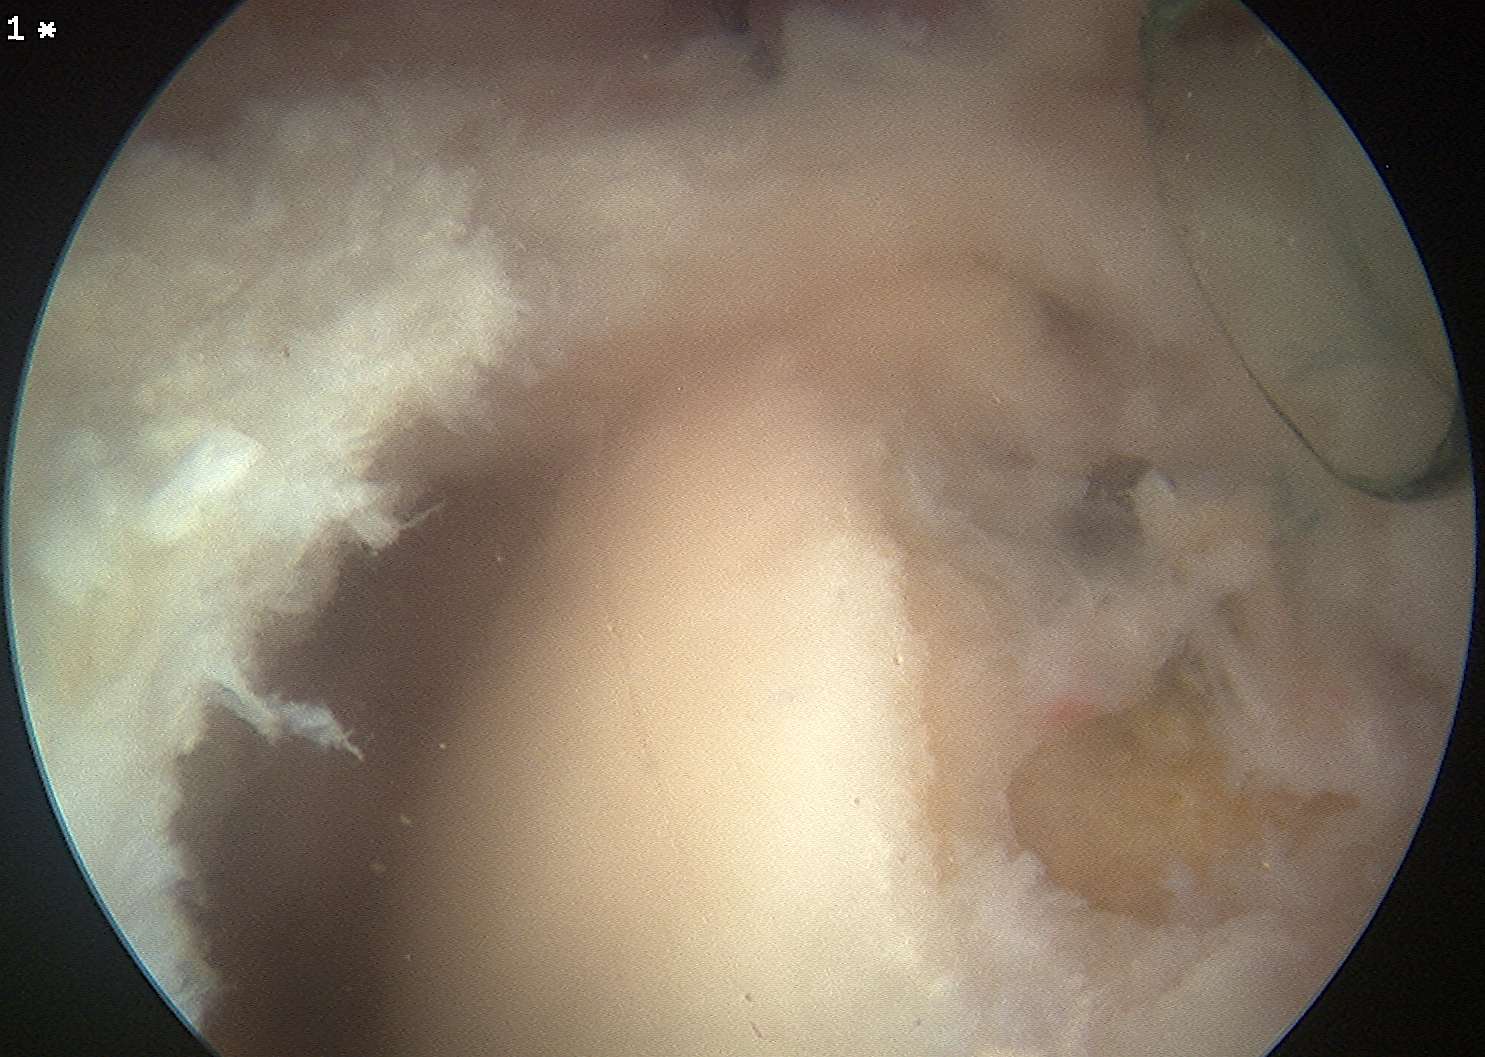

Glenohumeral joint

- inspect subscapularis

- evaluate SLAP / LHB tendinosis - tenotomy / tenodesis

Subacromial joint

- bursectomy for visualization

- acromioplasty if acromial spur

- debride footprint to bleeding bone

- +/- microfracture / K wire of footprint / marrow stimulation

Assess tear